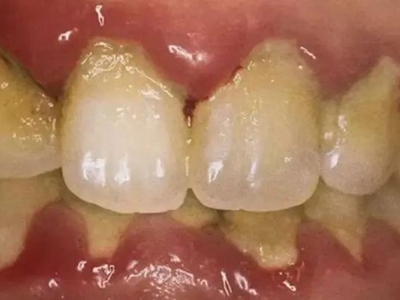

急性坏死性溃疡性龈炎症状图片

急性坏死性溃疡性龈炎起病急,病程短,常为数天至1-2周,以龈乳头和龈缘的坏死为其特征性损害,尤以下前牙多见,初起时龈乳头充血水肿,个别龈乳头顶端可发生坏死性溃疡,上覆有灰白色坏死物,中央凹下如火山口状。龈缘如虫蚀状,坏死区出现灰褐色假膜,擦去后可见出血创面。龈乳头被破坏后与龈缘成一直线,如刀切状。病损一般不波及附着龈,患处牙龈极易出血,疼痛明显并有腐败性口臭。